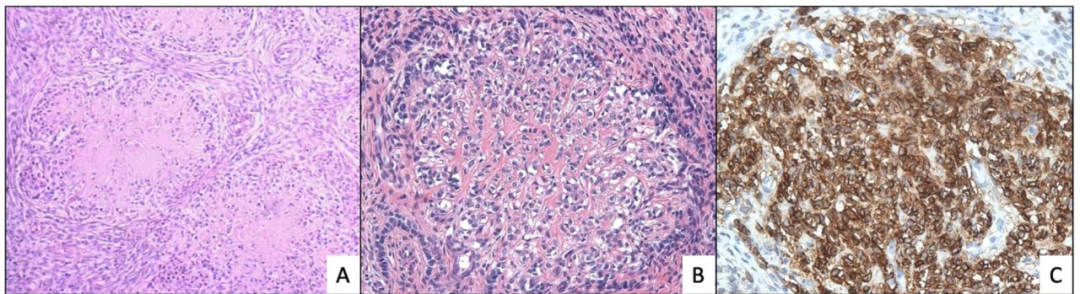

图3. 低级别子宫内膜间质肉瘤的形态学亚型。低级别子宫内膜间质肉瘤中伴“星爆样”表现的局灶平滑肌分化(A)、上皮样改变(B),免疫组化desmin阳性(C)。

(AB)本例为YWHAE-NUTM2融合的高级别子宫内膜间质肉瘤,低倍镜下呈浸润性生长、侵入肌层,并有淋巴-血管间隙浸润;高倍镜下,瘤细胞呈上皮样,核分裂增加。该例肿瘤免疫组化CD10(C)、ER(D)阴性,但Cyclin D1弥漫、强阳性(E)。

[伴YWHAE-NUTM2A/B融合的肿瘤](NUTM2A/B又名FAM22) 肿瘤多呈实性巢状,肿瘤广泛浸润、破坏子宫肌层(舌状浸润肌层),间质可见毛细血管网间隔,常见脉管侵犯、坏死,细胞圆形,体积较大(约小淋巴细胞5倍)[特征],胞浆较少,呈嗜酸性,胞核不规则,染色质空泡状,可见核仁(高级别,但异型程度<未分化癌),核分裂像活跃(常>10个/10HPF),部分病例含有低级别成分,常伴黏液样间质,少见子宫内膜样腺体、假乳头状、性索样、横纹肌样分化